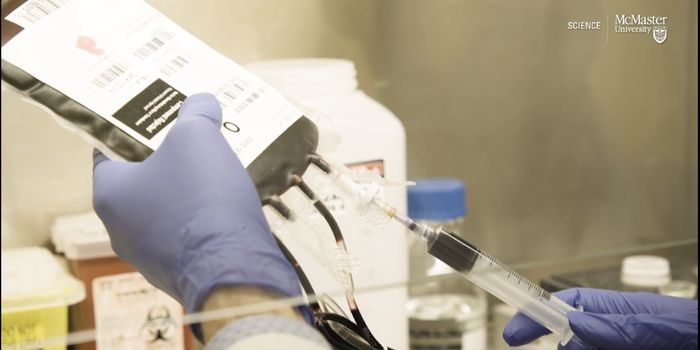

APR 30, 2024Cell & Molecular BiologyBlood is crucial to healthcare; as the population of the world ages, more medical procedures are being performed and the ...